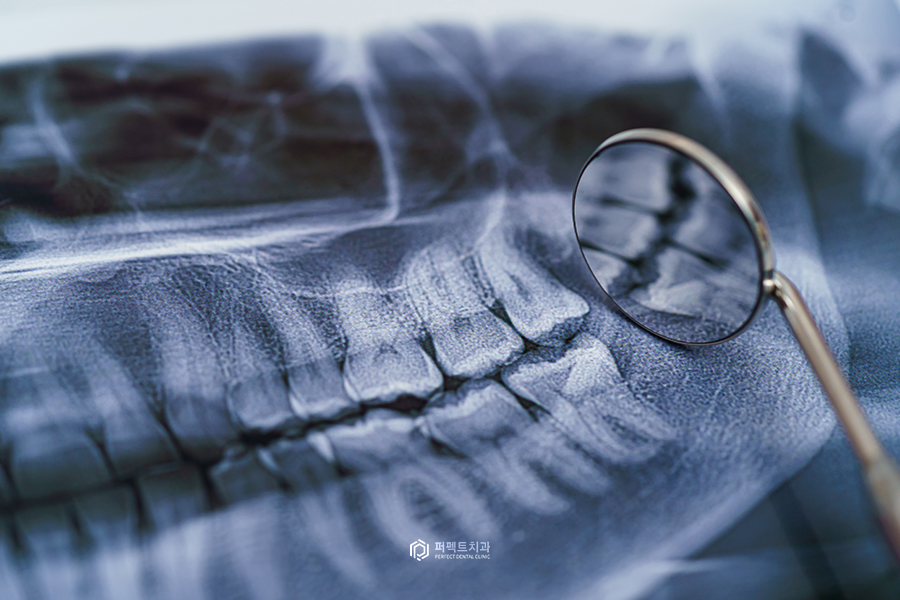

첫번째로 임신 중 치과치료에서 X-ray에 대한 부분을 많이 걱정하시는데 요즘에는 디지털화 되어 있기 때문에 엑스레이 사진 촬영에서 노출된 엑스레이의 양이 우리가 일상생활에도 노출되는 엑스레이 양과 비슷하다고 합니다. 그래서 태아에게 영향을 미칠 정도는 아니지만 본 원을 비롯해서 모든 치과들이 임산부의 태아를 보호하기 위한 '납방어복'을 구비하고 있습니다. 그래서 이러한 부분은 걱정하지 않으셔도 됩니다 :)